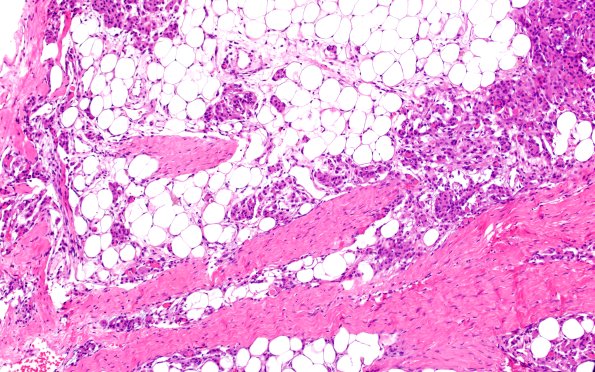

17C2 Meningioma, lipidized (Case 17) 1

There is extensive lipidization of tumor cells as well as presence of secretory material. (H&E)